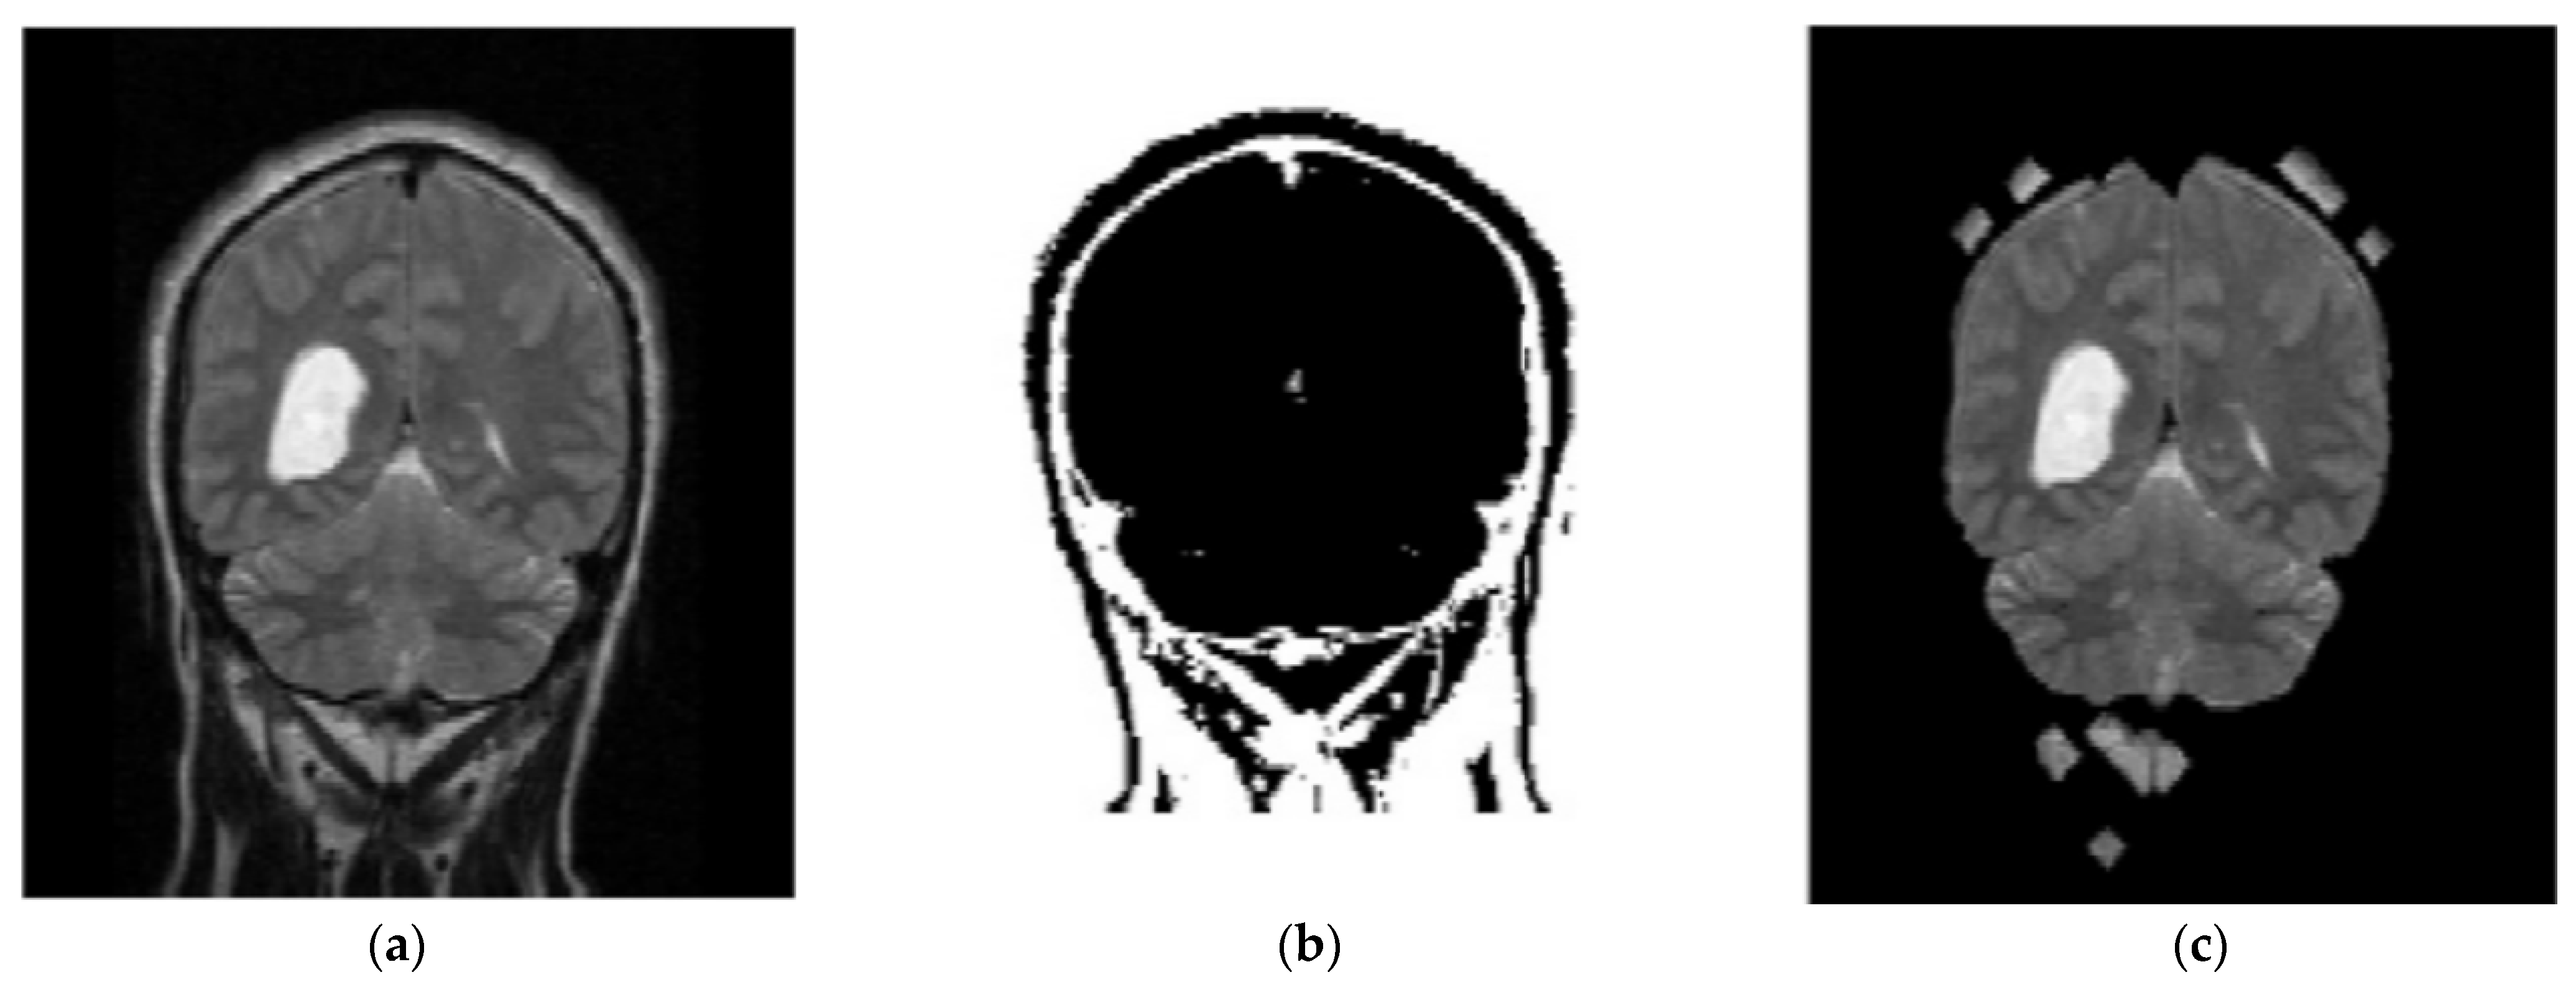

In the proposed segmentation approach, enhanced fuzzy c-means clustering is applied for brain tumor segmentation. In this method, an image’s N pixels are divided into fuzzy c clusters, where c is a positive number and n is a smaller number. Figure 4 and Figure 5 depict various sets of MRI brain images, such as the normal or original image, the binary level image, and the post-morphological operation outcome [37]. The segmentation process is taken as an enhanced version of the fuzzy c-means clustering (EFCMC) algorithm. This includes various stages, as shown in Figure 4 and Figure 5. After performing EFCMC, a final segmented tumor appeared. The proposed segmentation process took less time and was computationally less difficult than other methods.

Figure 4.

Brain MRI images: (a) normal; (b) binary; (c) after a morphological operation.